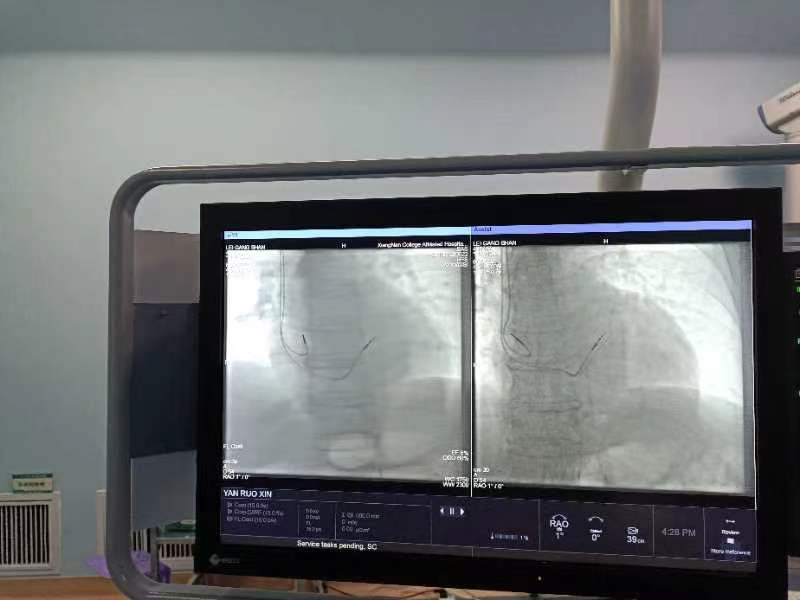

入院后,雷大爷被确诊为“III度房室传导阻滞”,心率只有30次/分,不到正常人心率的一半。据了解,III度房室传导阻滞是一种严重且危险的心律失常,严重可致晕厥、猝死。情况紧急,当晚心血管内一科主任廖昆团队立即为雷大爷急诊行临时起搏器植入术。

结合患者的年龄与身体状况,廖昆主任带领团队经过充分的术前评估及缜密讨论,完善术前检查,很快确定患者具有永久心脏搏器植入适应症。医生与患者家属充分沟通后,决定为患者植入永久性双腔起搏器。李林辉表示,“该起搏器可使用15年,超长待机时间,具有自动调整频率功能,虽然手术比单腔起搏器难度更高,但能最大限度保证雷大爷心脏正常起搏,大大减少术后心衰等并发症,改善其预后生活质量。”

手术在局部麻醉下进行,廖昆团队凭借精湛的技术不到一小时便顺利完成手术。术后患者雷大爷反应状态良好,心率恢复至正常水平,不日将出院。